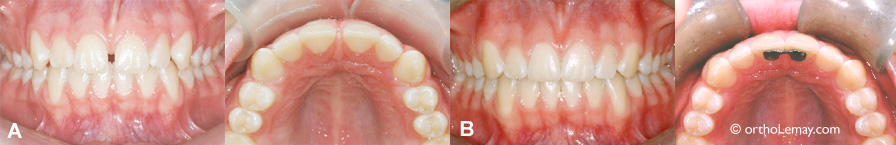

• (A) Dentition avec 2 latérales étroites (“grain de riz”) avant le traitement.

• (B) Après les corrections, les espaces sont distribués de façon optimale pour permettre d’élargir les latérales. Les autres aspects e la malocclusion ont aussi été corrigés.